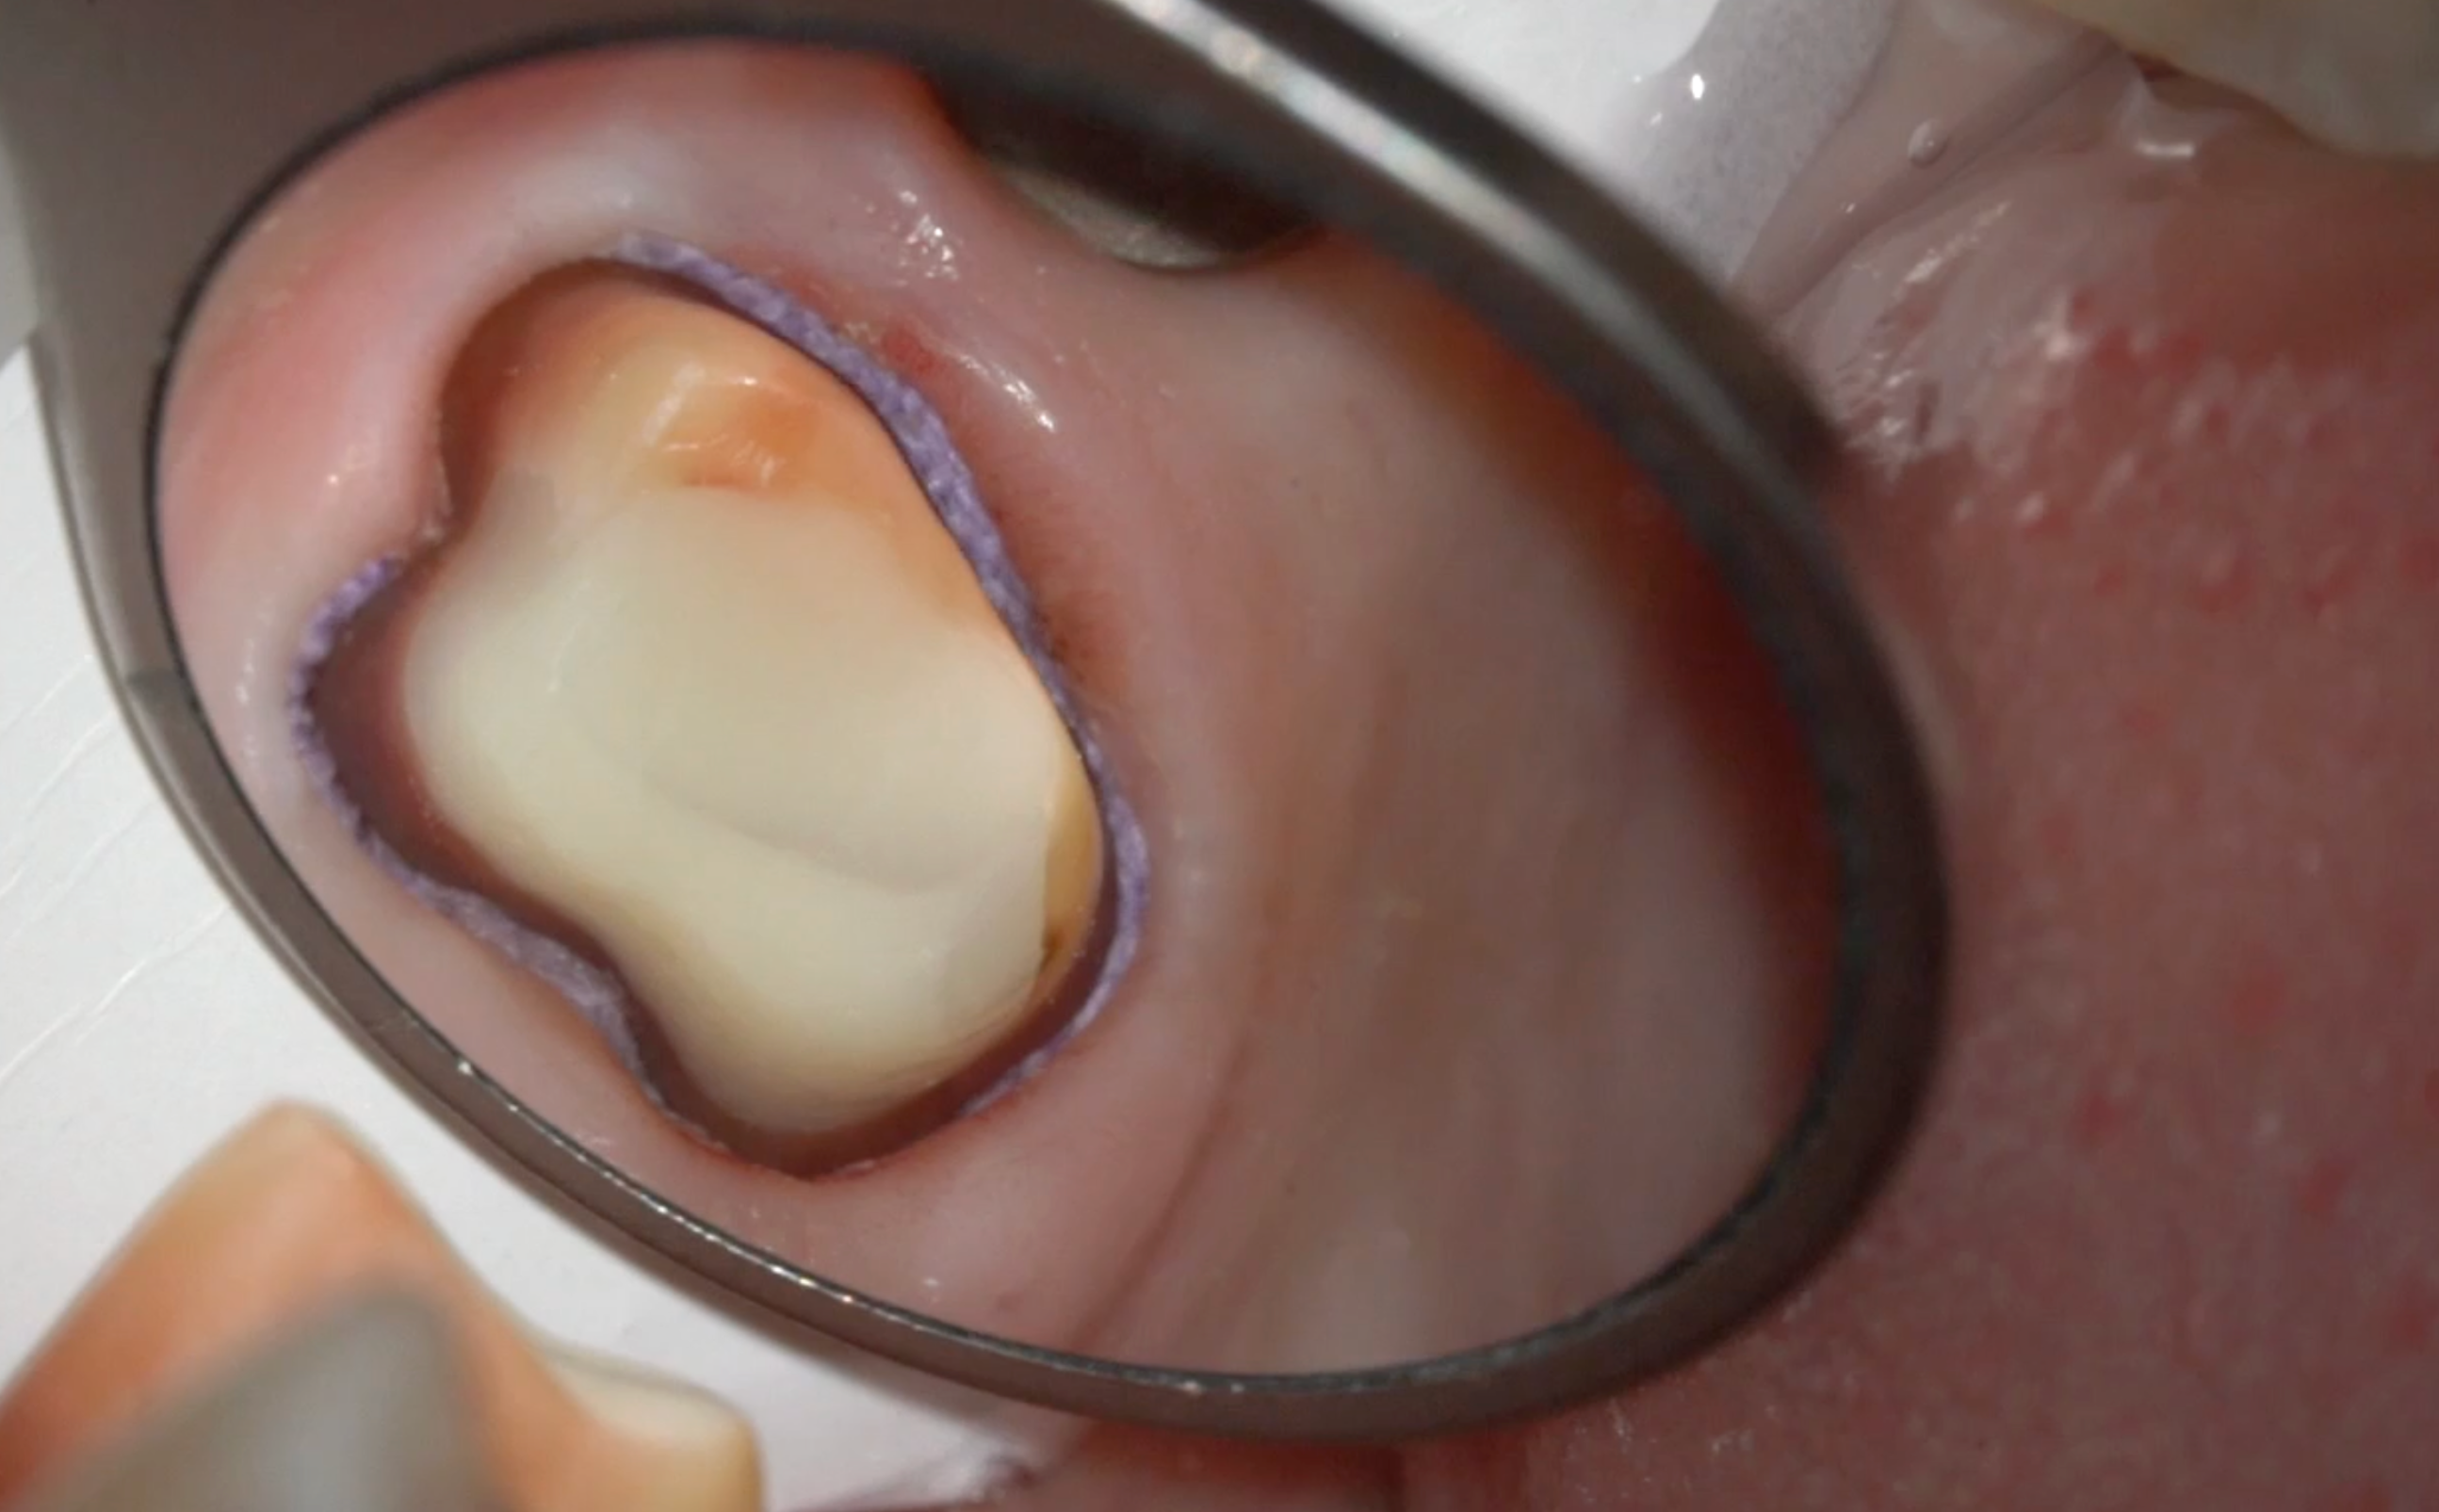

Протезирование в эстетически значимой зоне на зубах с опорой на имплантаты

Оценка эстетических и функциональных рисков при протезировании зубов и имплантатов, которые приводят к неудаче лечения. Восстановление структуры зубов и ортодонтическая подготовка перед протезированием. Моделирование профиля прорезывания супраструктур и временных реставраций у зубов и имплантатов. Подготовка мягких тканей перед протезированием. Методы изготовления временных реставраций для немедленной нагрузки.

Практическая часть включает в себя изготовление временной коронки на имплантат прямым методом.